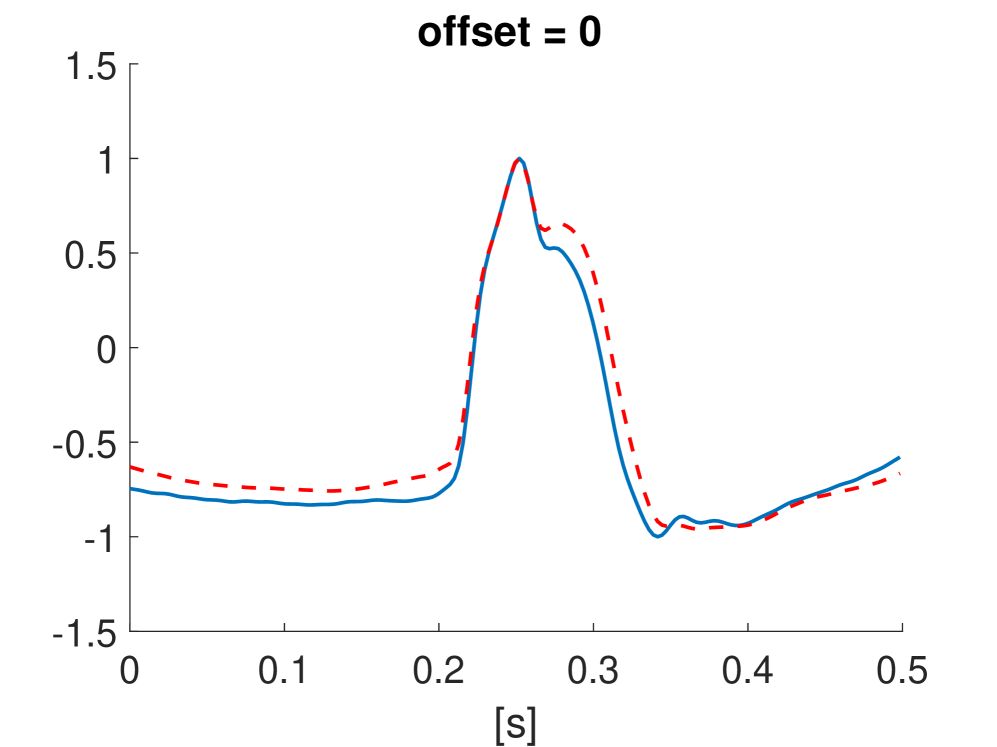

Fig. 10 shows the result in input space of moving along the first principal components in the latent feature space. As original base point we take a normal beat signal, i.e. corresponding to a hidden unit on the bottom right of Fig. 9(a). The smooth transition between the beat patterns allows for interpretation of the first principal components. This allows a clinical expert to understand on what basis the paced beats are separated by the principal components and if this basis has a physiological meaning. In order to investigate the separated region of the latent space at the top of Fig. 9(b) we start from a paced beat pattern and vary along the third principal component. This allows us to see which sort of heartbeat patterns are responsible for this specific distribution in the latent space.